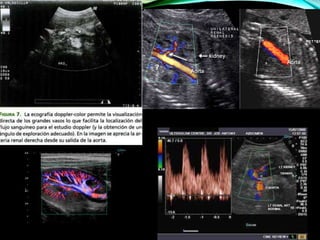

ECOGRAFÍA DOPPLER Y

DOPPLER COLOR

 Estudiar de modo no invasivo patología vascular como el

• 48.

Microgránulos de galactosay a. palmítico aumento de las señales eco en los vasos sanguíneos (burbujas micrométricas de agua) presencia, dirección y características del flujo sanguíneo + estudios Doppler concluidos. POTENCIALES DE SEÑAL ECOGRÁFICA